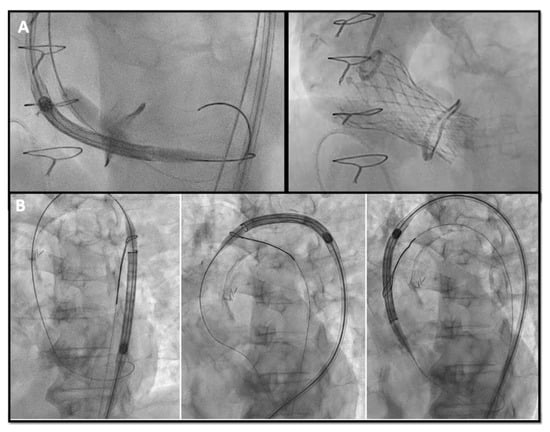

Bioprosthetic heart valves (BHV) have been increasingly implanted instead of mechanical valves in patients undergoing surgical aortic valve replacement (SAVR). Structural valve deterioration (SVD) is a common issue at follow-up and can justify the need for a reintervention. In the evolving landscape of interventional cardiology, valve-in-valve transcatheter aortic valve replacement (ViV TAVR) has emerged as a remarkable innovation to address the complex challenges of patients previously treated with SAVR and has rapidly gained prominence as a feasible technique especially in patients at high surgical risk. On the other hand, the expanding indications for TAVR in progressively younger patients with severe aortic stenosis pose the crucial question on the long-term durability of transcatheter heart valves (THVs), as patients might outlive the bioprosthetic valve.